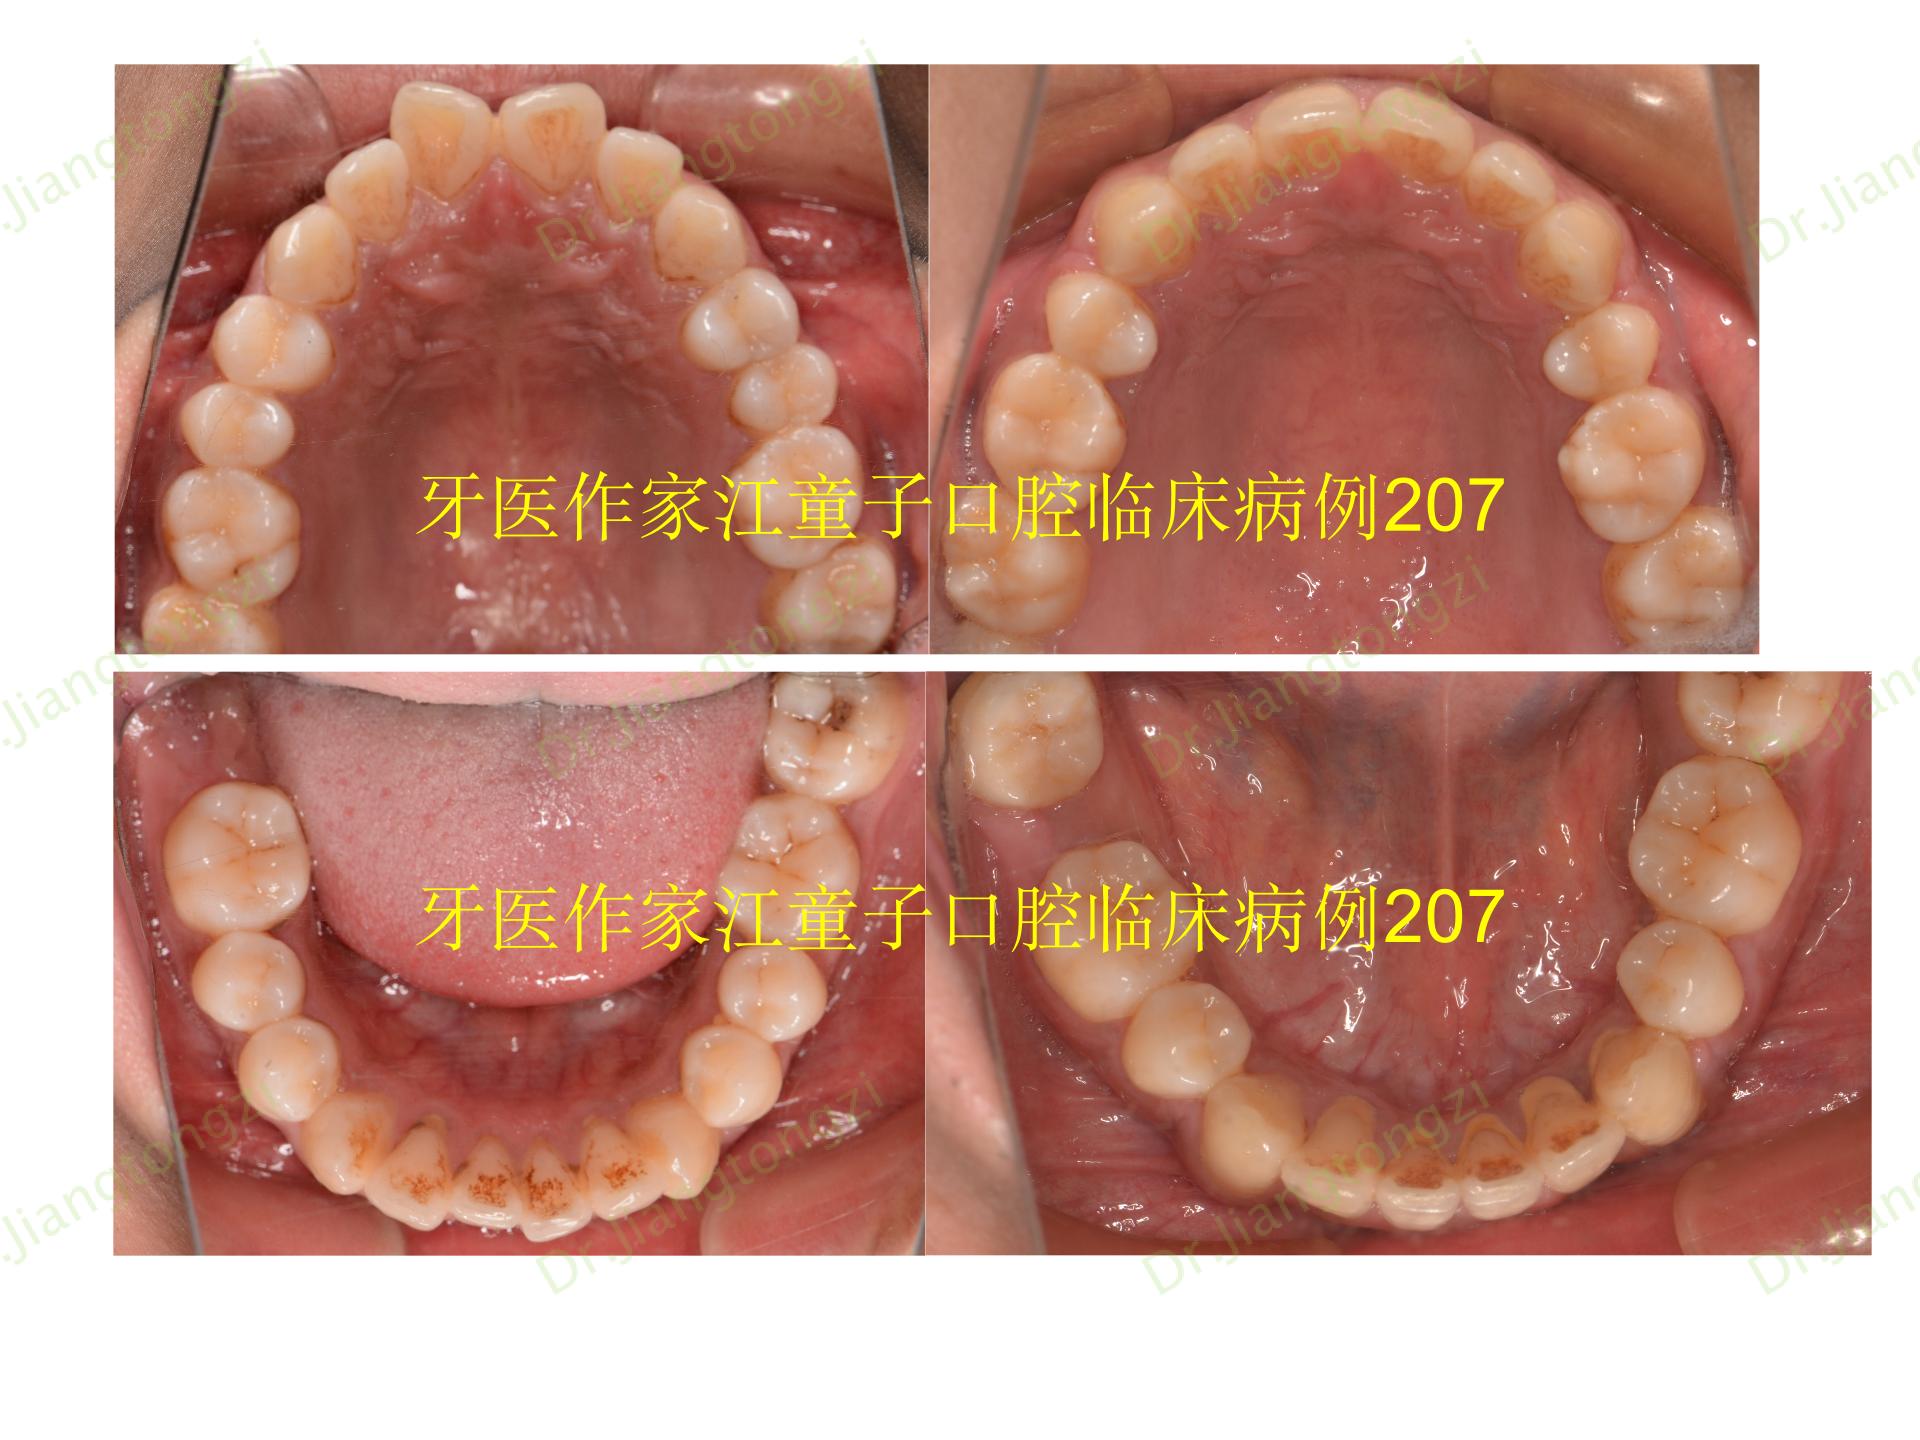

《正畸案例41:正畸中的骨开裂与骨开窗》

图片尺寸1920x1440

《正畸案例41:正畸中的骨开裂与骨开窗》

图片尺寸1920x1440